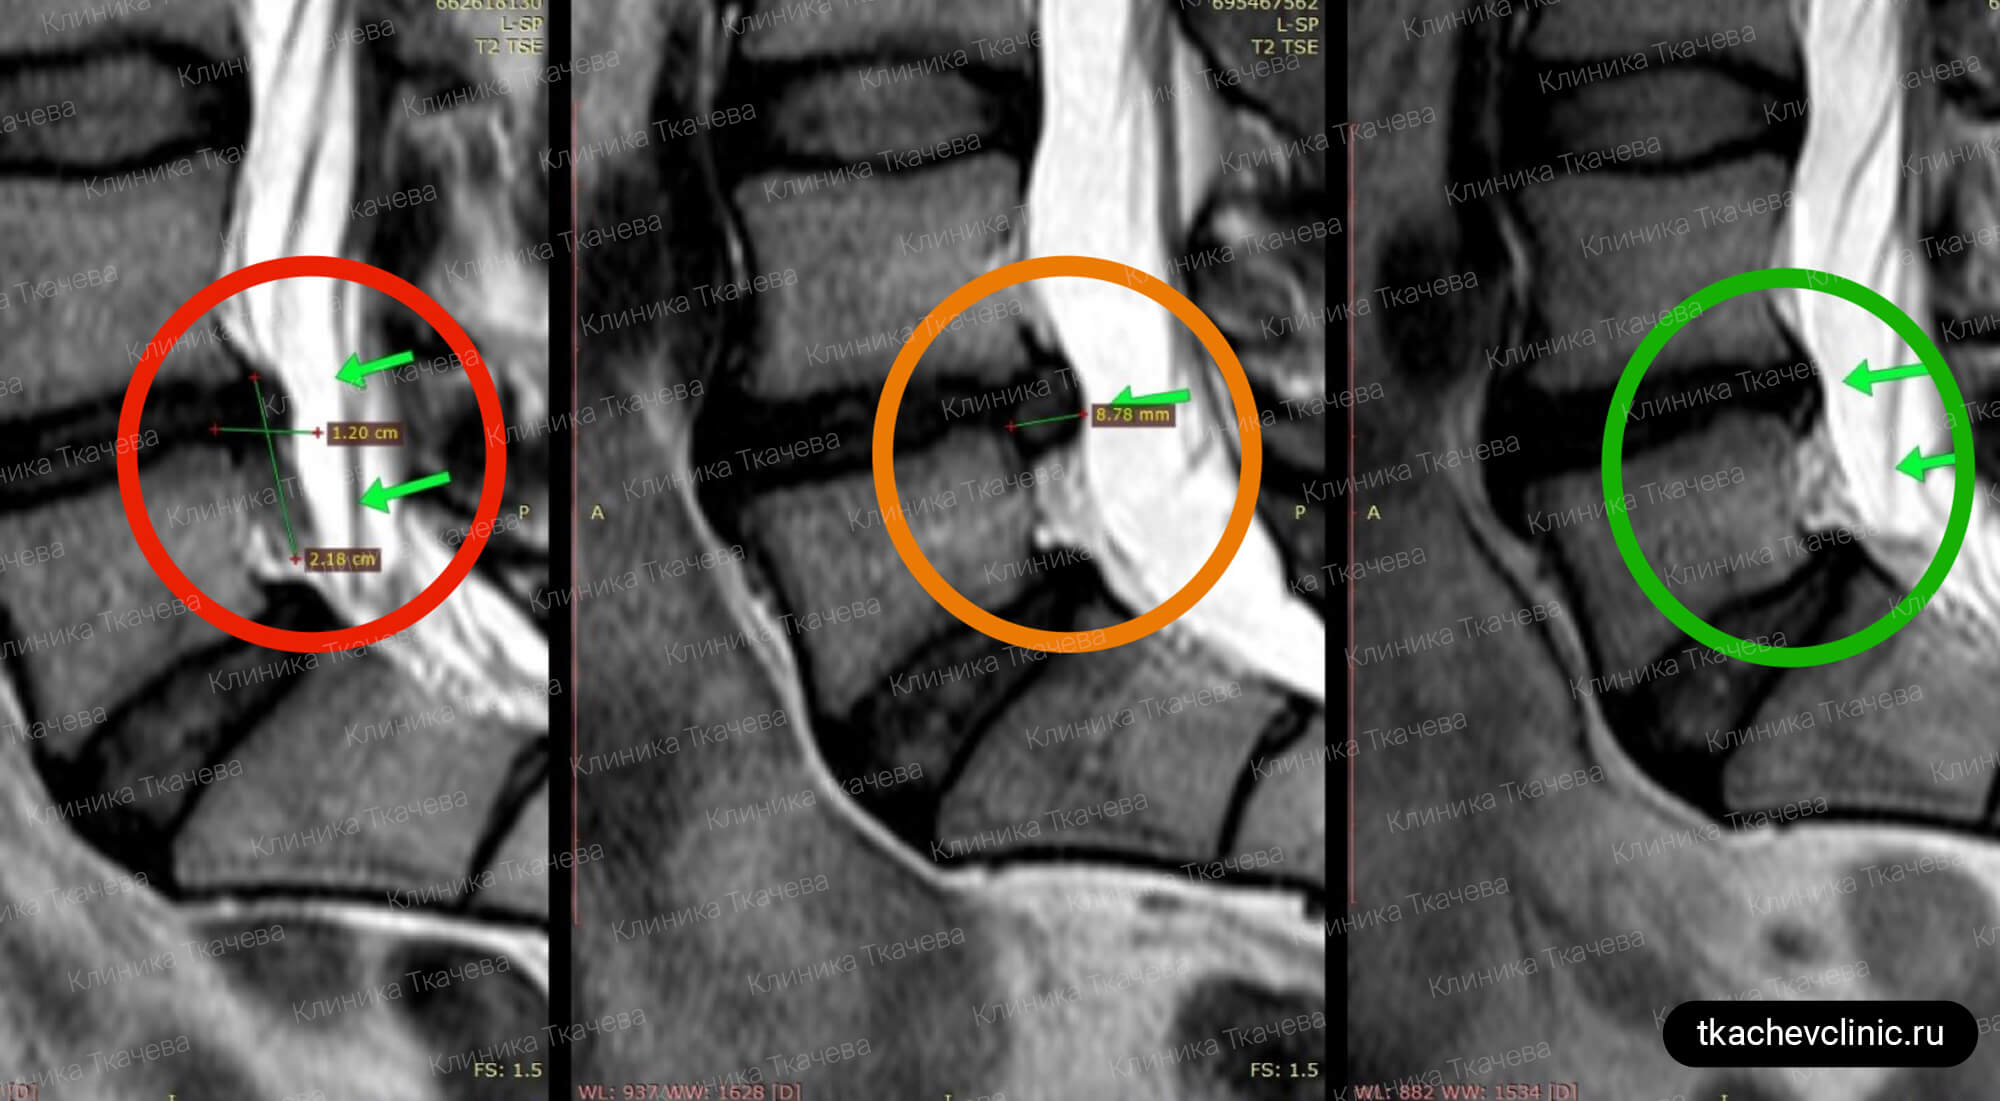

Латерализация грыжи